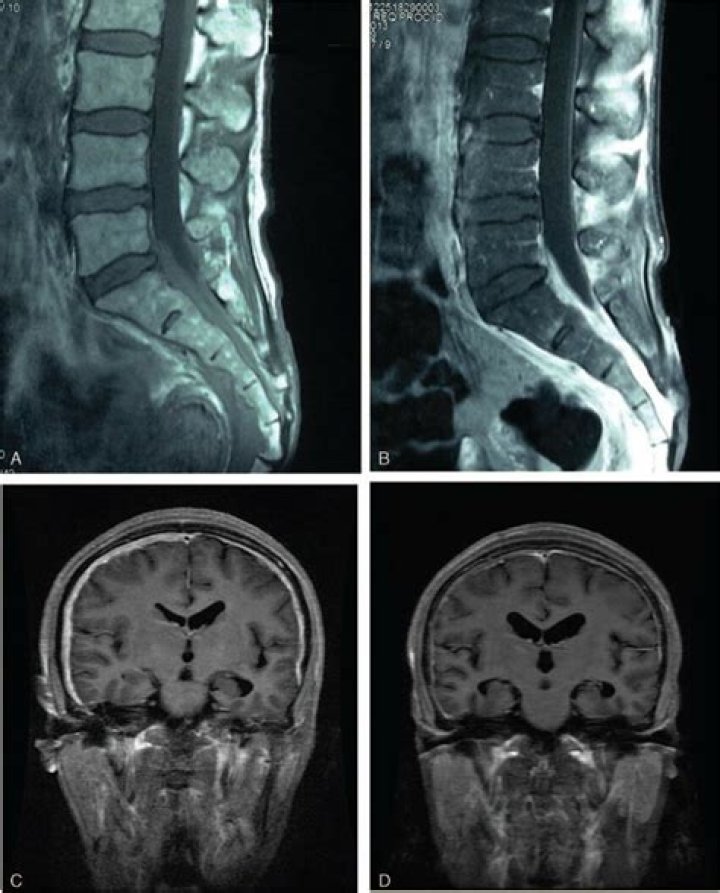

Hypertrophic pachymeningitis is a rare form of diffuse inflammatory disease that causes thickening of the dura mater. It can involve the cranial or the spinal dura or both.

Idiopathic hypertrophic pachymeningitis (IHP) is a rare disease caused by thickening of either the intracranial or spinal dura mater, or rarely both simultaneously. Chronic headache, multiple cranial nerve (CN) palsies, and cervicodynia are the most common clinical manifestations.

Abstract. Pachymeningeal enhancement, synonymous with dural enhancement, is a radiological feature best appreciated on a contrast-enhanced magnetic resonance imaging (MRI). The vasculature of the dura mater is permeable, facilitating avid uptake of contrast agent and subsequent enhancement.